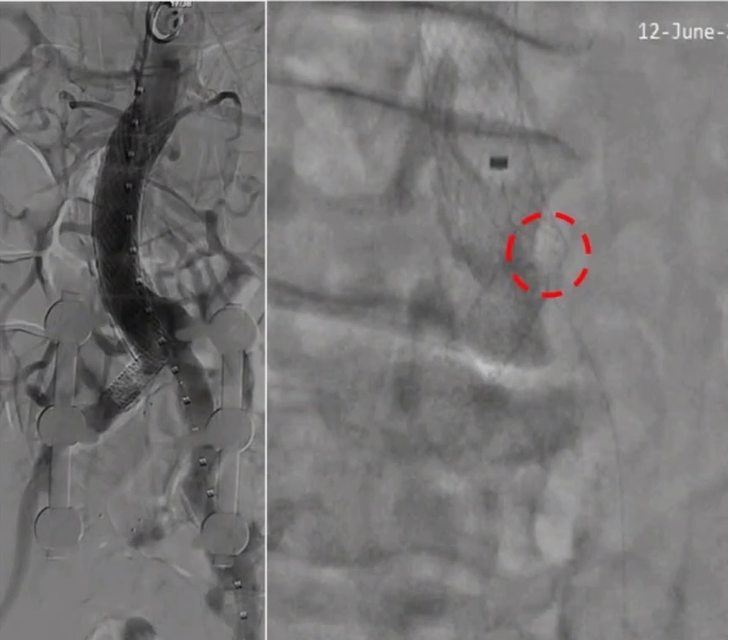

术前造影:

左侧导丝要经过右侧原裸支架后面进入腹主动脉,右侧导丝要确保从原有支架内全程通过,不能从网孔内通过。所以,右侧通过裸支架时,导丝成袢通过。导丝通过后,造影确认。

更换导丝后,双侧分别置入球囊扩张导管扩张,目的是确认:1)球囊是从支架内通过;2)球囊扩张后,之前横向走行的髂动脉裸支架形态能否被矫正;3)对对侧球囊是否有压迫

双侧球囊同时打起,观察其在腹主动脉内相对位置